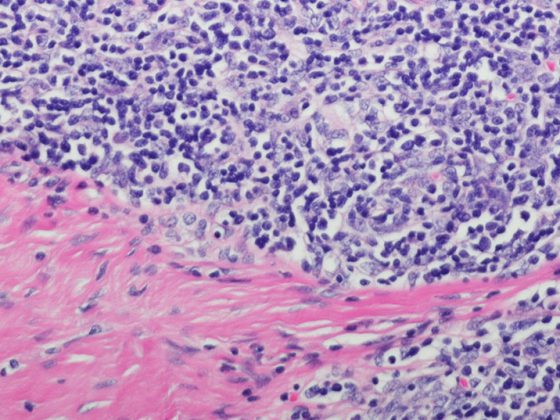

thymustumor_istock-599127854

• Mediastinale Tumoren

Thymustumore erkennen und State-of-the-Art behandeln